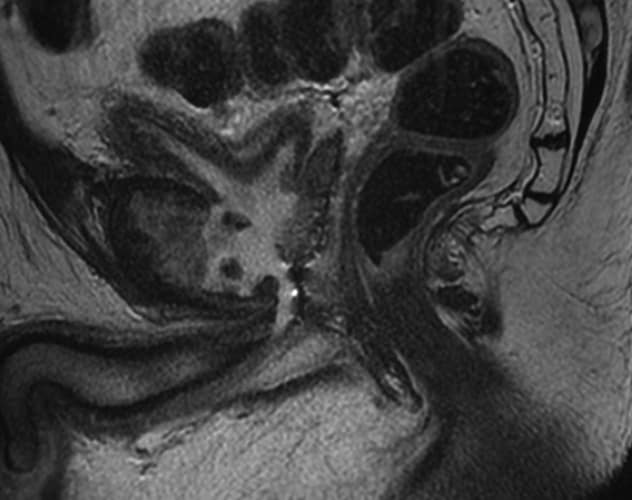

MRI images of urosymphyseal fistula in the sagittal (left) and coronal (right) planes.

Often endoscopic treatment is performed in men with posterior urethral stenosis. Repetitive or aggressive manipulation of the posterior urethra after radiation can lead to devastating sequelae. Most notably, there is a small risk of developing urosymphyseal fistula. In these cases, a direct fistula from the posterior urethra to the pubic symphyseal joint develops. Resultant progressive and recalcitrant osteomyelitis of the adjacent bone can occur. Men may present with debilitating groin pain, obstructive urinary symptoms, urinary tract infections and sepsis.

- Nearly all patients presented with debilitating groin pain with ambulation (24 of 25; 96%) and were diagnosed with pelvic MRI.